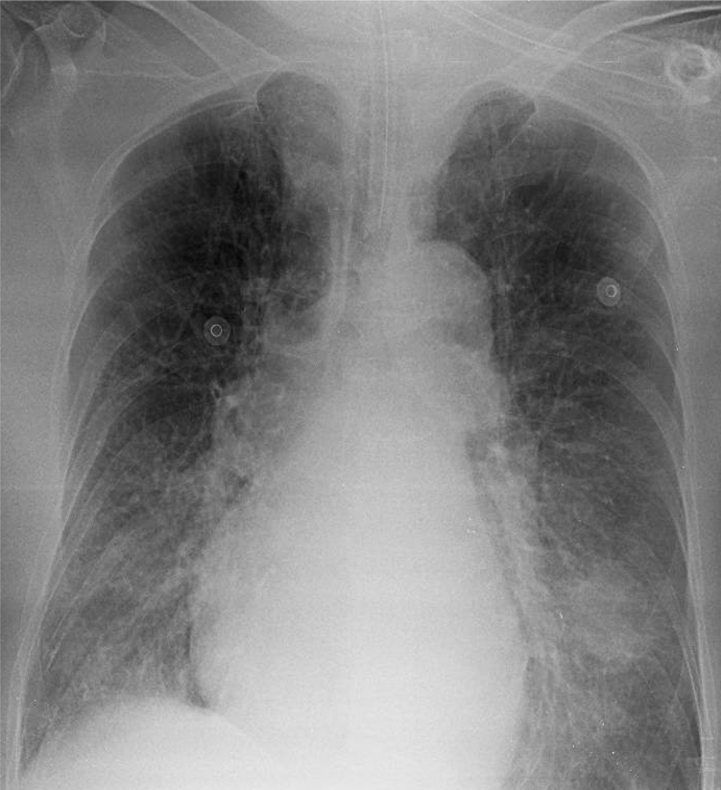

1-Có ống thông nội khí quản 2-Thâm nhiểm mô kẻ rải rác hai phổi => Viêm phổi 3-U thùy dưới phổi (T) 4-Tim to